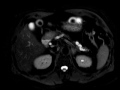

Main duct Intraductal Papillary Mucinous Neoplasm (IPMN)

MRI and CT images nicely demonstrate diffuse dilatation of the main pancreatic duct with ectatic side branches, compatible with main-duct IPMN.